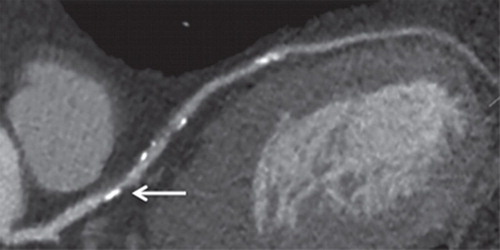

En este estudio se buscó la presencia de micro y nanoplásticos (MNP) en las placas ateromatosas extraidas por endarterectomía carotídea en pacientes asintomáticos: en  el 58% de los casos se encontró polietileno y en el 12%, polivinilo. En el seguimiento de 34 meses, la presencia de MNP en la placa carotídea se asoció con un mayor riesgo de infarto de miocardio, accidente cerebrovascular o muerte por cualquier causa. New England Journal of Medicine, 7 de marzo de 2024.